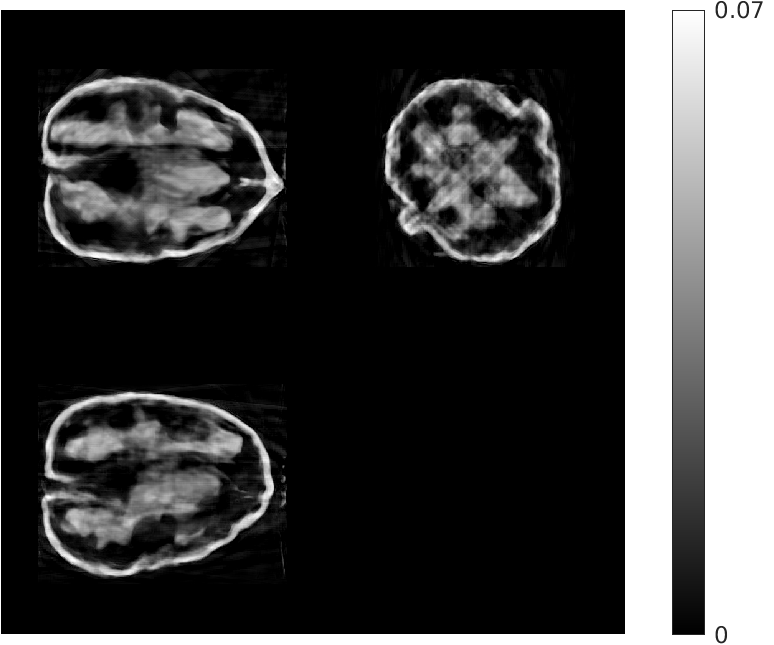

Fig. 5 shows walnut 1 from our test dataset being progressively reconstructed from 8 projections across the stages of our algorithm; as the stages progress, more features are restored in the reconstructed walnut, until the improvements become incremental. The residual streaking artifacts outside the walnut are mitigated in the reconstructions from the third and fourth stages.

| Stage 1 | Stage 2 |

![]() |

| (a) (MAE: 0.32) | (b) (MAE: 0.29) |

| Stage 3 | Stage 4 |

| (c) (MAE: 0.27) | (d) (MAE: 0.26) |